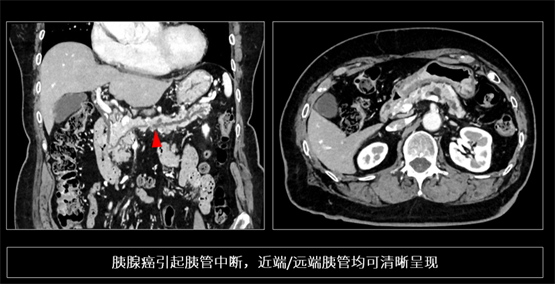

胰腺癌被称为“癌中之王”,早期病灶往往呈现等密度,且解剖位置深,极易漏诊。传统 CT 因软组织对比度与分辨率的相互制约,难以捕捉胰管的微小截断或局限性狭窄。依托 PIQE的高空间分辨率与低噪声特性,INSIGHT Pioneer 能够捕捉到胰腺实质的细微纹理改变及胰管的早期形态学变化。在一位早期胰腺癌患者的影像(下图)中,胰管出现细微中断,且上下游胰管呈现连续而清晰的形态,基于这一隐匿性病变的识别,临床在进一步检查中将其证实为早期胰腺癌。这样的胰管变化,在传统 CT上几乎不可能这么清楚。